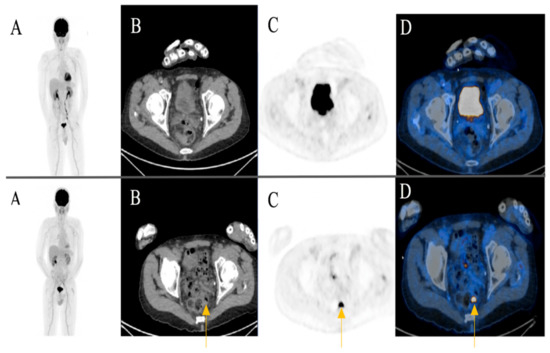

Among the patients with additional primary cancers, an indeterminate subcutaneous nodule was seen in the left breast of an 81-year-old female patient in post treatment surveillance (initially with metastatic cutaneous melanoma stage IV). The reporting physicians recommended an ultrasound-guided biopsy for further evaluation. The biopsy revealed an invasive ductal breast cancer (Figure 3) (Case 1).

Figure 3. An 81-year-old female patient initially with metastatic cutaneous melanoma stage IV (pT2a N3 M1b). (A) Maximum intensity projection (MIP); (B) Computed Tomography (CT) axial of chest; (C) Positron Emission Tomography( PET) axial of chest; (D) Fused images PET/CT axial of chest. First row: FDG-PET/CT performed for surveillance after treatment without evidence of metabolically active recurrence, nodal or distant metastasis. Contamination at injection site cubital on the right upper extremity. Second row: Six months later, a morphologic and metabolic progredient subcutaneous nodule in the left breast was seen (yellow arrow). An ultrasound-guided biopsy was subsequently recommended for further evaluation. The biopsy revealed an invasive ductal breast cancer.